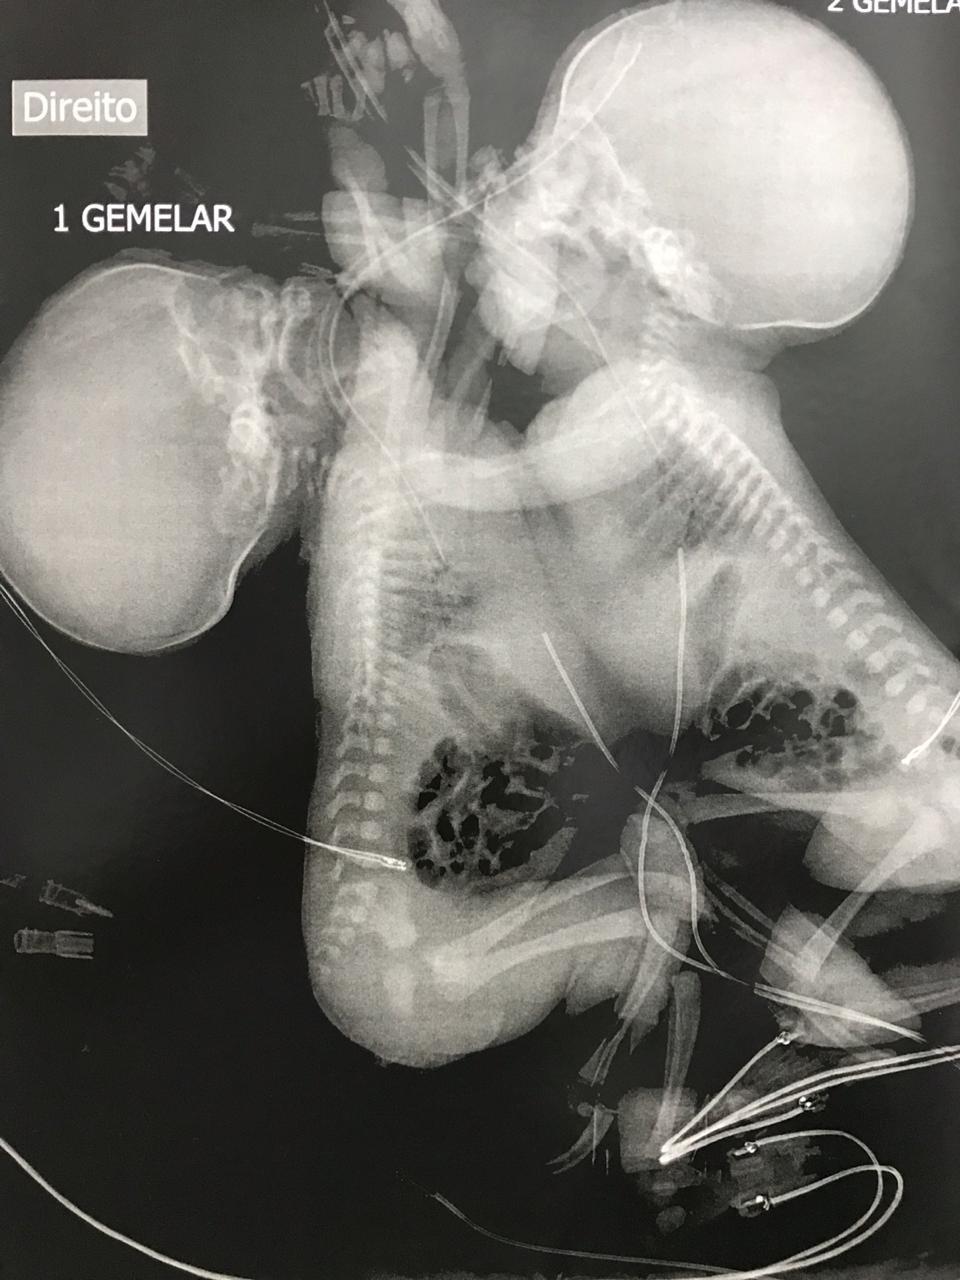

Após descobrir uma gestação de gêmeas siamesas toracópagas, com cardiopatia complexa, pois as duas tem apenas um coração, onde a viabilidade de vida extrauterina é quase nula, levou uma moradora da cidade a recorrer à Justiça para interromper a gravidez, que inclusive poderia colocar sua vida em risco.

Casos como este são raríssimos. Dados médicos indicam que gêmeos siameses toracópagos ocorrem em cerca de um nascimento a cada 250 mil. Ainda assim, o número corresponde apenas a casos de nascidos vivos, sem incluir situações de inviabilidade total como a registrada em Prudente.

Os pareceres ressaltaram que os fetos eram unidos pelo tronco e compartilhavam um único coração com cardiopatia grave, quadro apontado pela literatura médica como absolutamente incompatível com vida extrauterina. Assim, a interrupção não configuraria crime e seria necessária para resguardar a saúde física e mental da gestante.